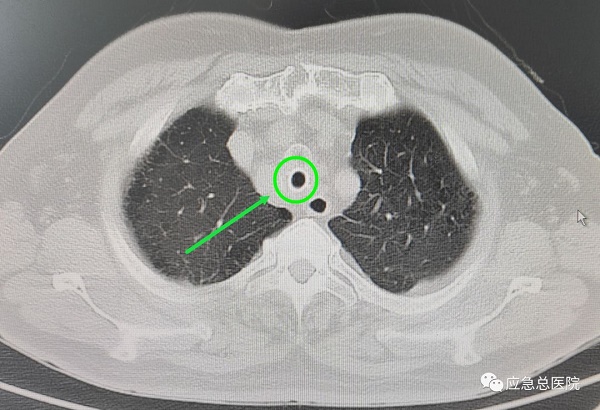

全身麻醉下,王洪武教授应用王氏插入法,仅5秒钟就成功插入硬质镜,建立了治疗和抢救通道,电子支气管镜下,可以看见原来的裸支架已经埋入气管粘膜内,突入的组织使得管腔仅有20%的空间能够流通空气,在张楠教授等专家的协助下,应用硬镜铲切、硬镜扩张、ND-YAG激光、高频电、氩气刀、二氧化碱冻取、球套扩张等多种技术配合,切除气管内增生的肉芽组织、部分异常粘膜,将原裸支架烧断、分解,抽丝剥茧,最后将整个支架完整取出,气管狭窄程度减轻为50%,手术结束后患者迅速苏醒,感到憋气症状明显缓解。

5天后,患者气管粘膜恢复,局部坏死物排出,再次气管镜局部治疗,清理管腔,经再次评估及精确测量后为患者放置了一枚气管硅酮支架,至此狭窄段管腔恢复至正常管径的80%,气喘症状完全缓解。患者激动地说:“能让王洪武教授这样的顶级专家亲自为我做手术,我太幸运了,是应急总医院给了我第二次生命啊!”